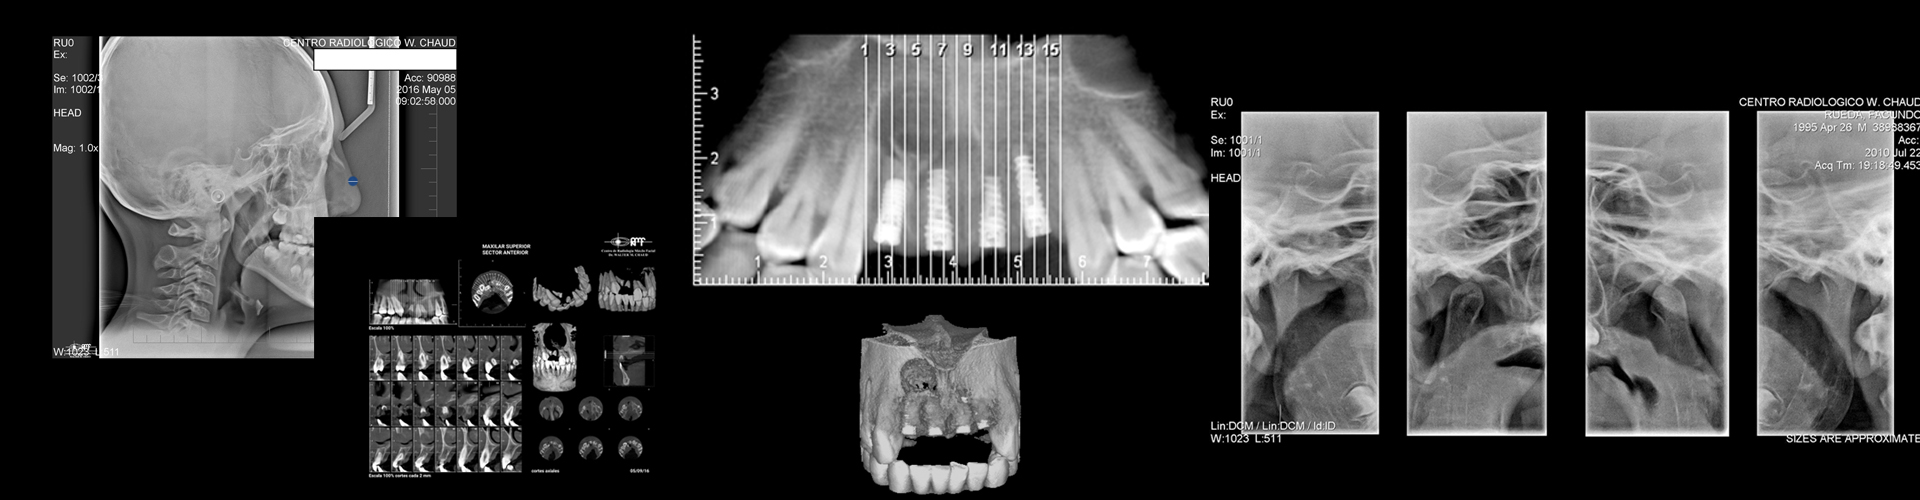

CENTRO RADIOLOGICO

DR. WALTER M. CHAUD

Se dedica con exclusividad a la RADIOLOGÍA ODONTOLÓGICA desde el año 1986. Lleva el nombre de quien fuera su fundador, y es administrado desde sus orígenes y hasta el presente por la Sra. Carmen H. Haack , bajo la dirección, desde el año 1.997, del Odontólogo Dr. Germán A. Villani y la colaboración desde 1.998 de la Od Martinez Maria Isabel.

Todas las radiografias se entregan impresas en películas.